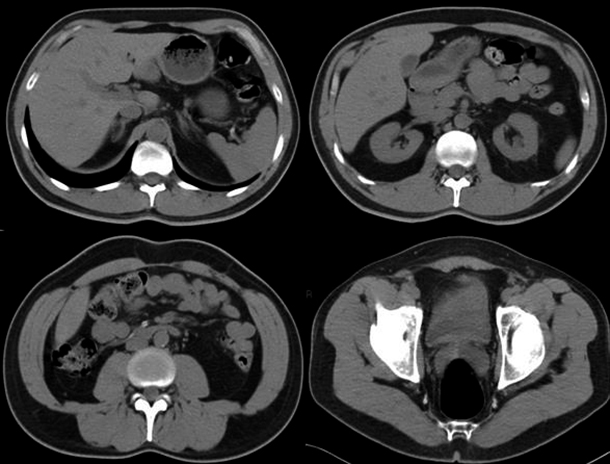

Fig. 3. Angio TC. Reconstrucción en 3D.

El contraste EV es importante para la detección y la evaluación de las complicaciones vasculares (angioTC) y para la documentación de la necrosis pancreática, que es la fase terminal de la lesión isquémica de la glándula. Se pueden hacer reconstrucciones en 3D que son muy útiles para el análisis conjunto con los cirujanos tratantes (Fig. 3) (3).